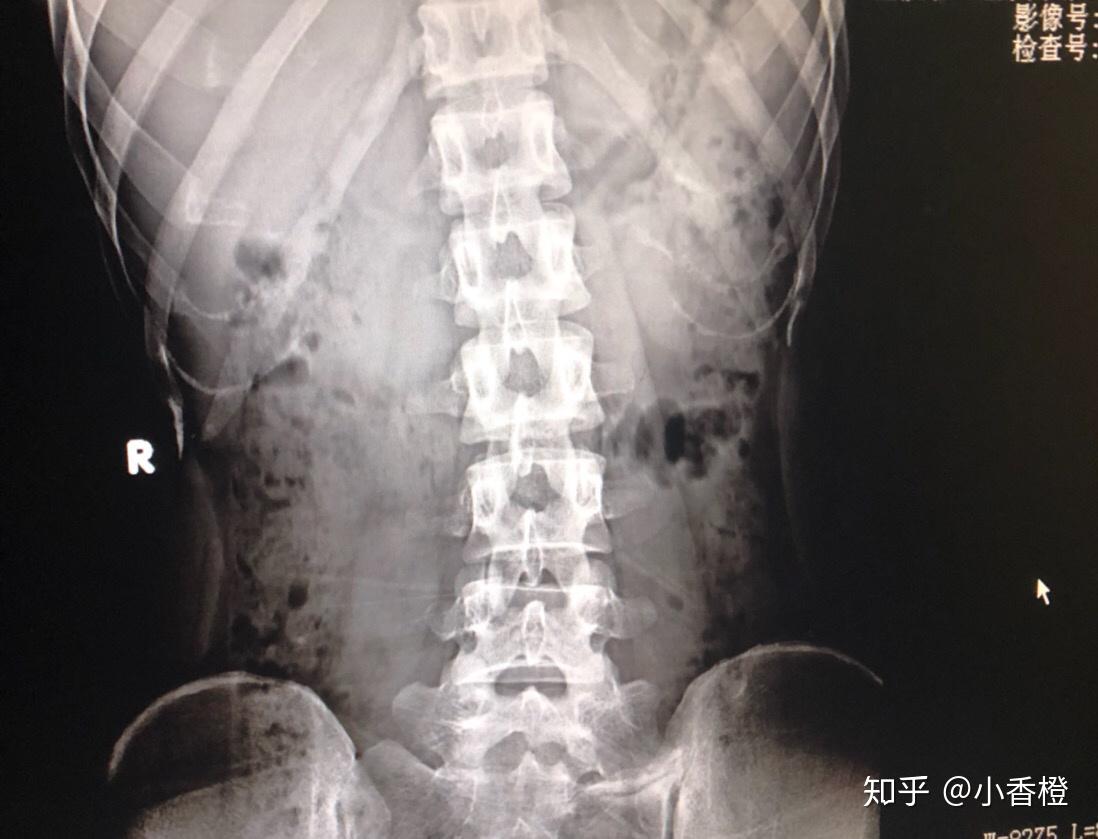

腰部拍片

腰痛,拍了个片子,请大神帮我看一下,有什么问题么

腰椎x线照片.

人体下腰椎部分的x光片